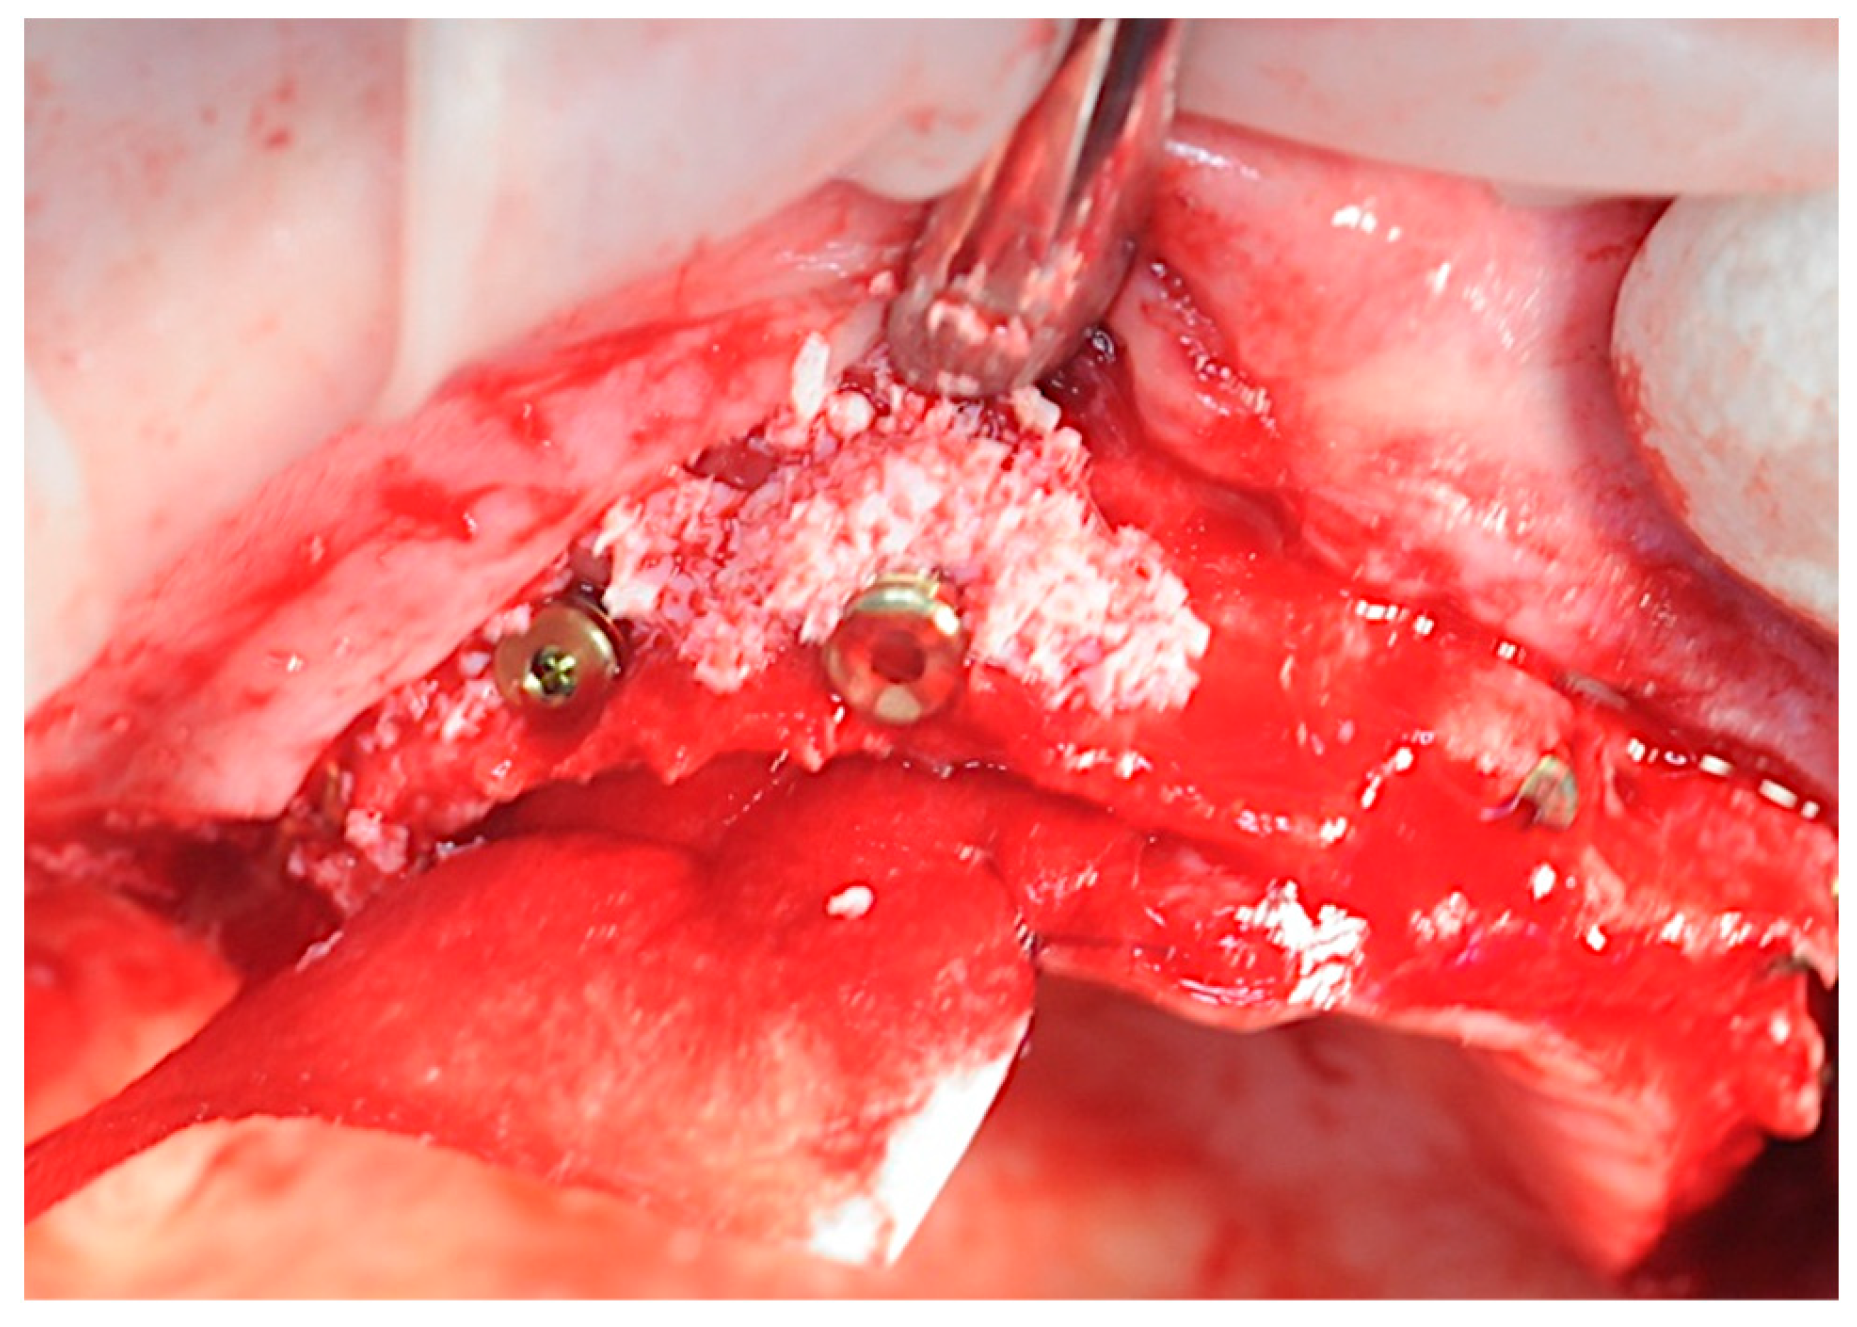

2.3. Re-Entry Surgery